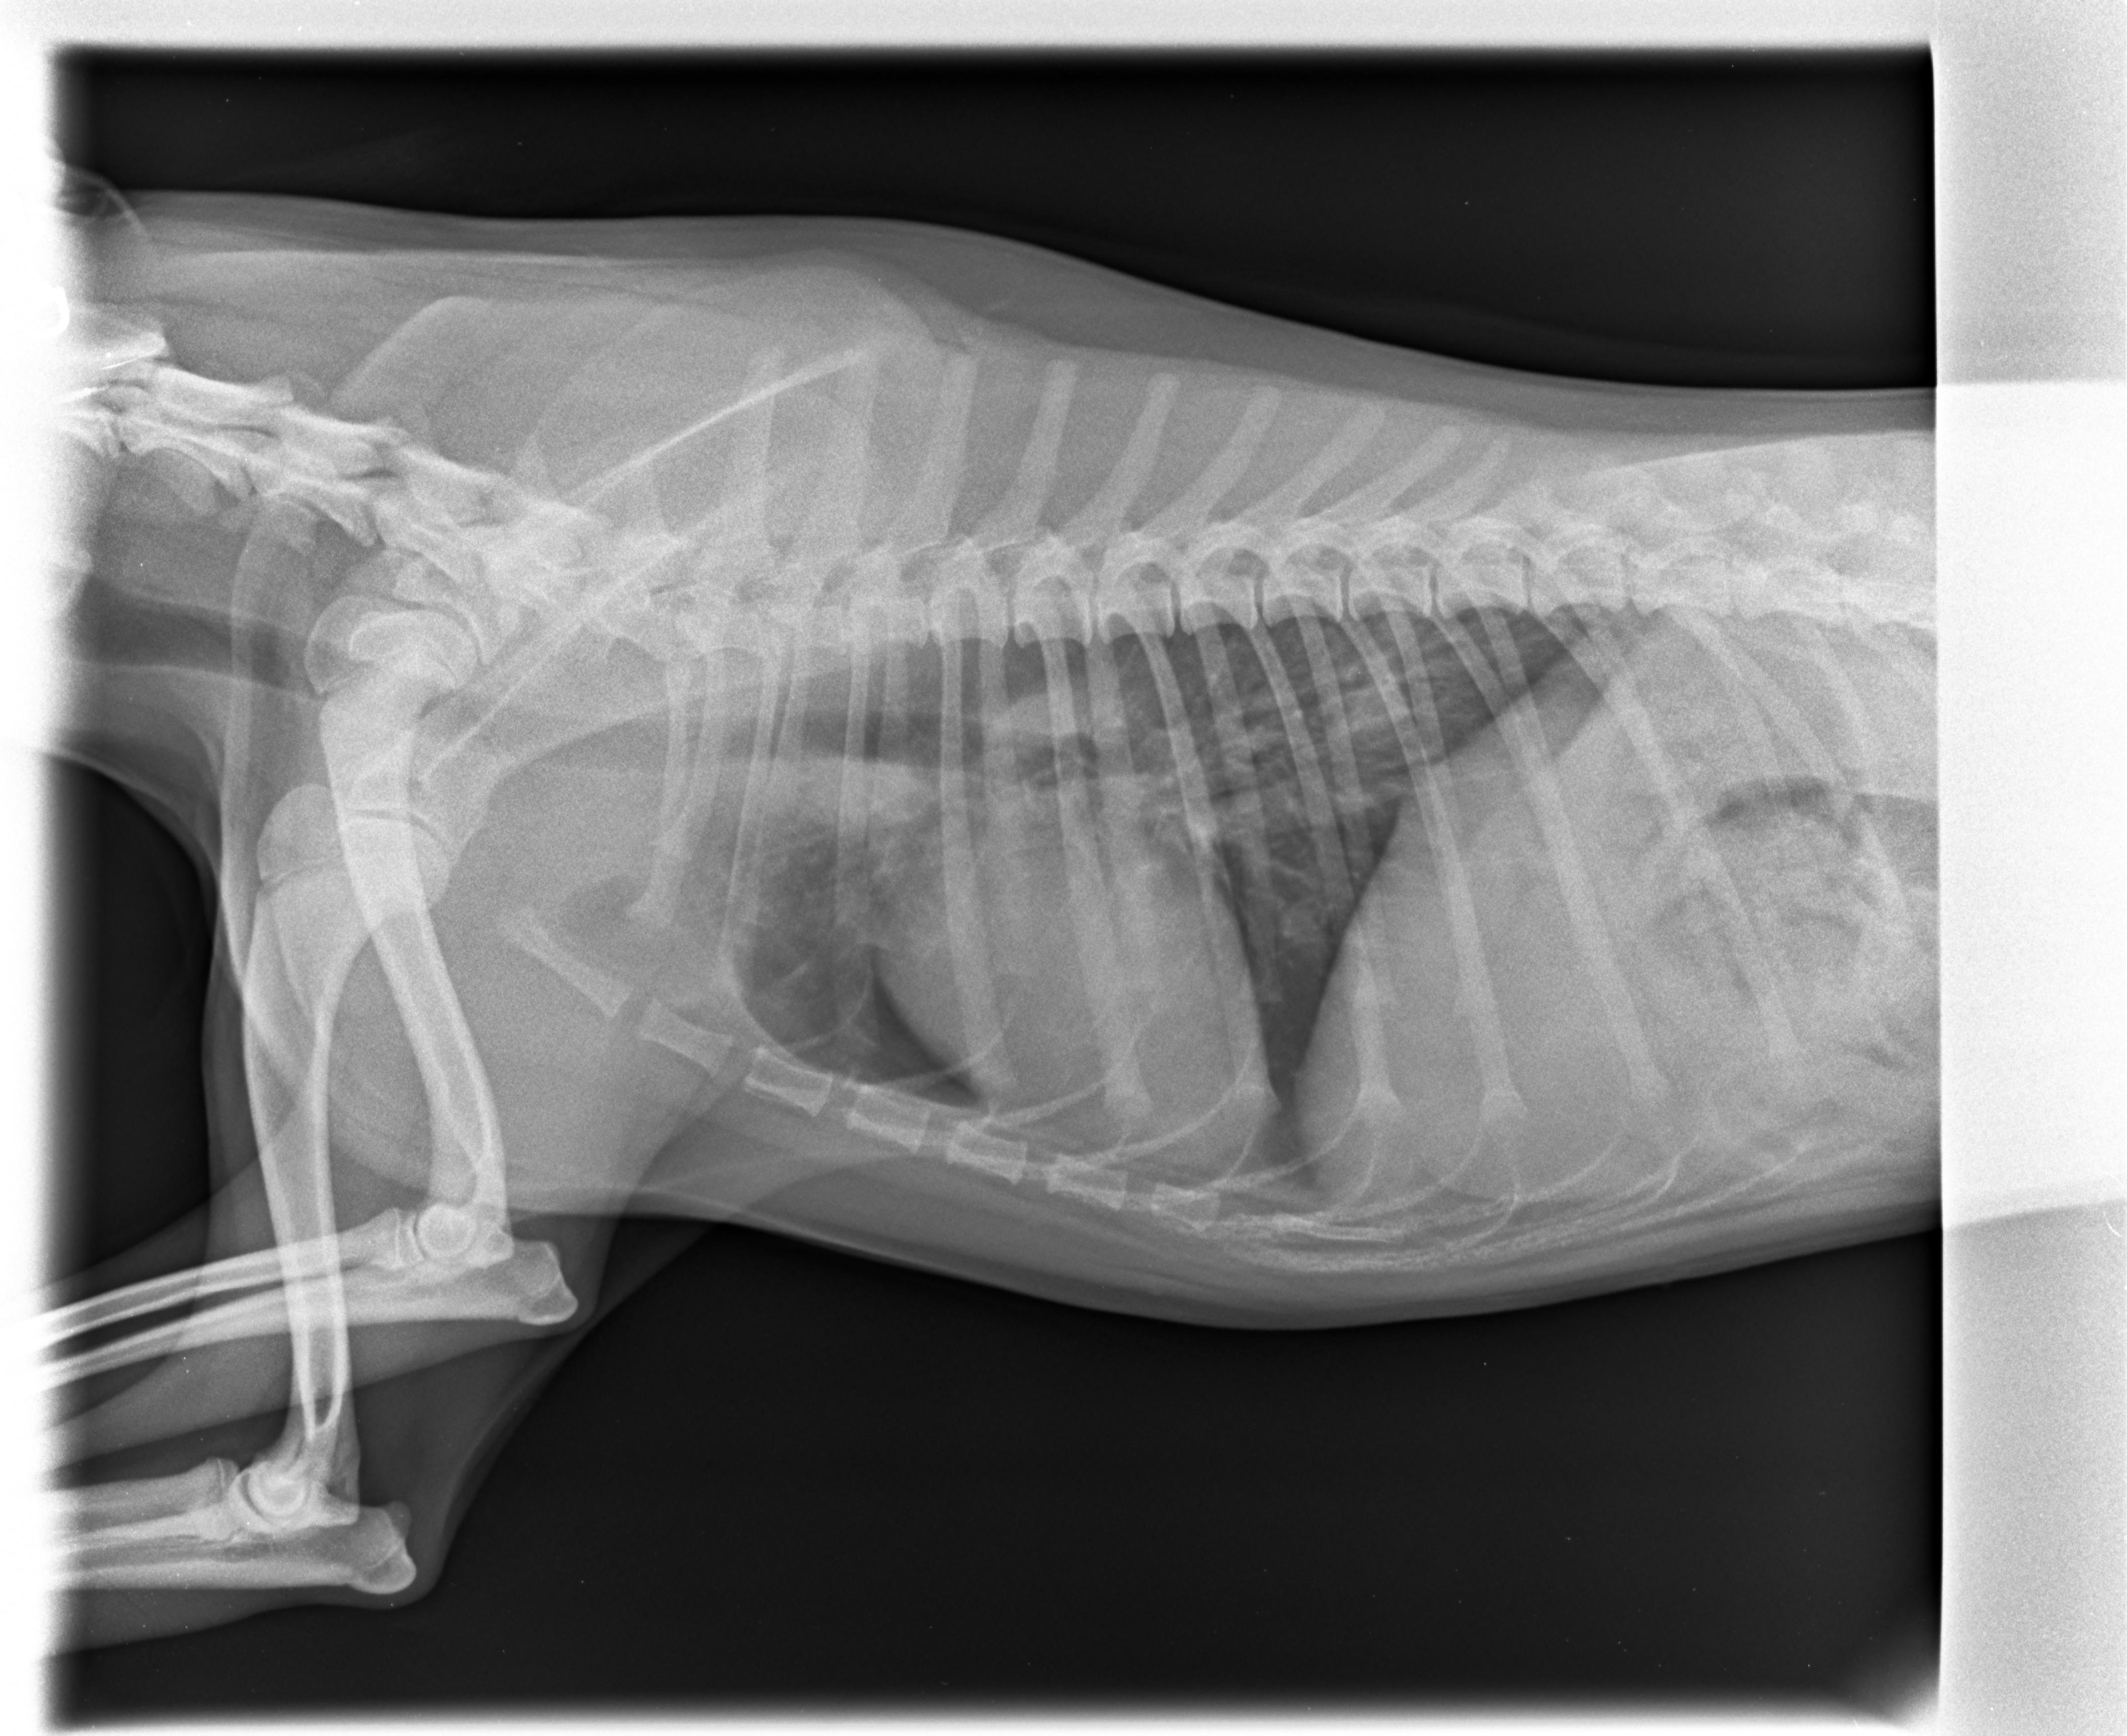

Das Röntgenbild eines 5 Monate alten Hundes. Die Wachstumsfugen, hier am Ellbogen zu sehen, schließen sich beim jungen Hund nicht gleichmäßig. Sie sind die Schwachstellen des Knochens. Foto: Sonja SchmittDie Wachstumsfugen sind also die Schwachstelle des Knochens beim jugendlichen Hund. Stauchungen und Frakturen innerhalb der Wachstumsfuge haben dramatische Auswirkungen. Die Wachstumsfugen schließen sich nicht gleichmäßig, Es ist ein langwieriger Prozess, der je nach Körpergröße früher oder später abgeschlossen ist. Bei einem großen Hund kann dieser Prozess bis zum 12. Lebensmonat dauern.